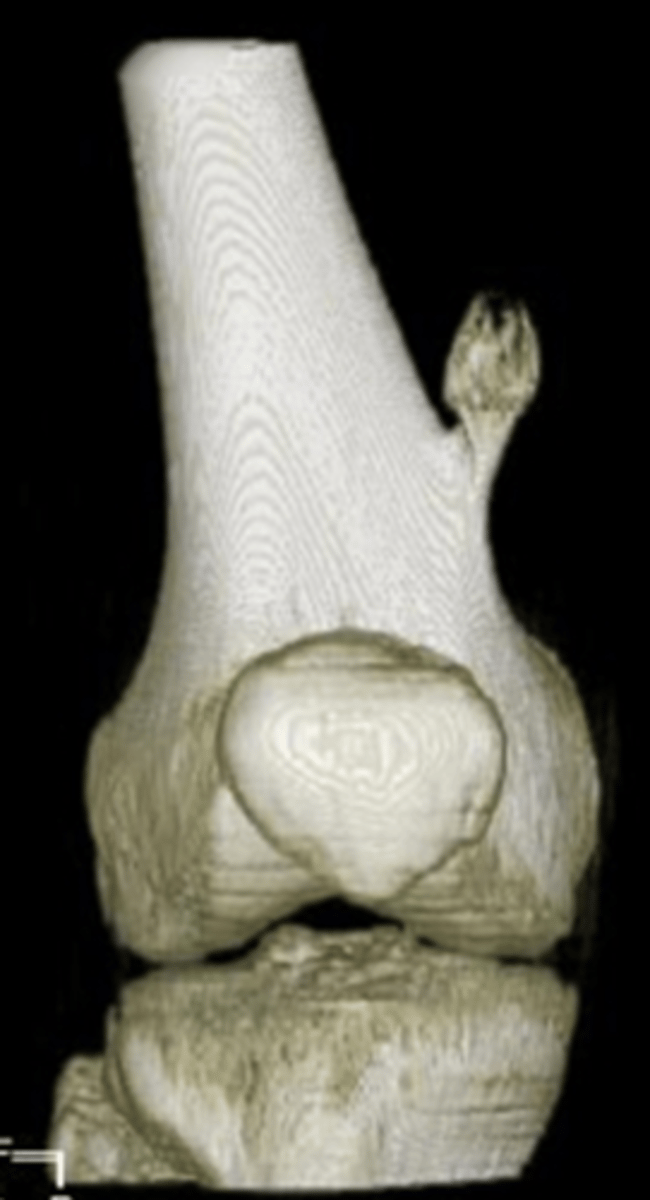

60

New cards

Pathologic fracture

Non-ossifying fibroma with _____

<p>Non-ossifying fibroma with _____</p>